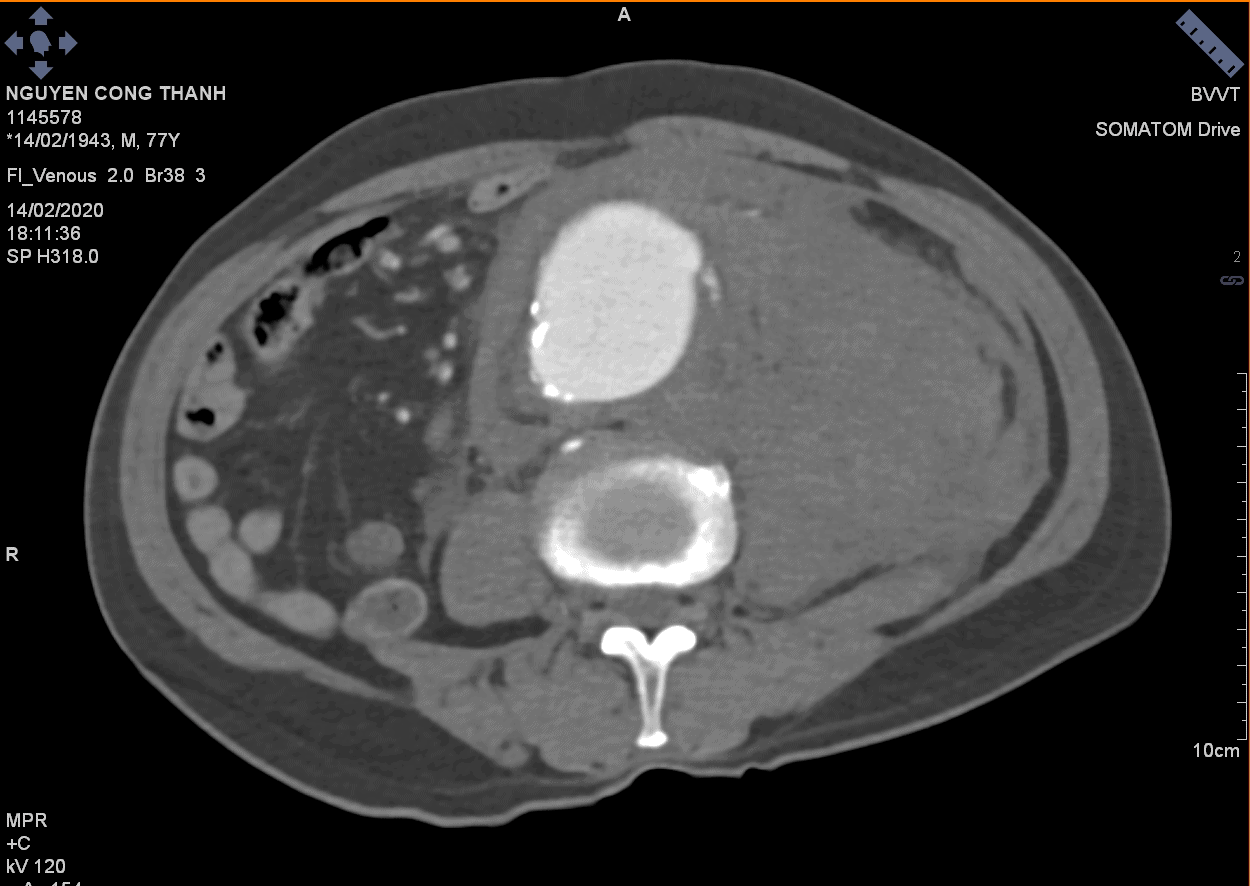

Vỡ phình ĐM chủ bụng

» Thông tin: Nam giới – 77 tuổi.

» Lâm sàng: Đau bụng cấp.